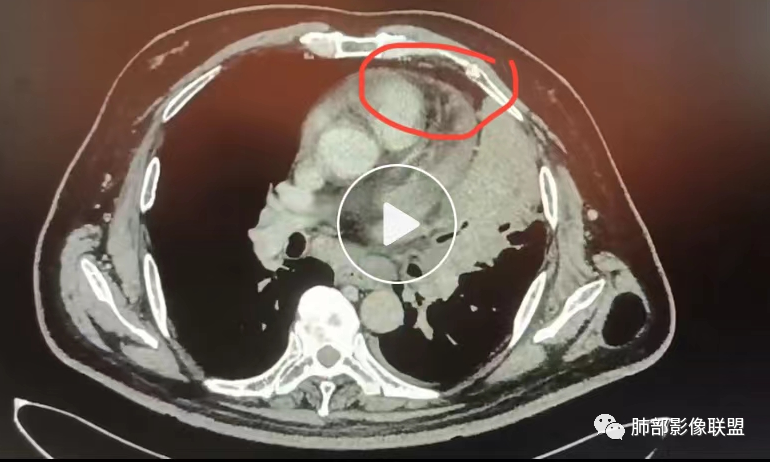

三、影像表现:左肺上叶多发片状高密度影,散在,边缘模糊,支气管壁稍增厚,中轴间质、小叶间隔增厚、有结节感,左肺上叶前段病灶可见胸膜增厚,部分小支气管不能分辨;右肺上叶后段混合磨玻璃结节,边界清,邻近胸膜凹陷;纵膈淋巴结肿大;心包增厚;左侧少量胸水。此外,扫及右侧胸腔内甲状腺肿;左侧肩胛骨旁肌群内脂肪瘤。

四、综合分析:老年男性,以咳嗽咳痰为主要临床表现,无发热,白细胞正常,影像表现为左肺上叶片影,前段结节影、胸膜增厚、部分小支气管不能分辨。左肺上叶中轴间质增厚、小叶间隔增厚、结节感,肺门纵隔见肿大淋巴结,尽管肺部病病灶边缘特征不典型,但高度疑及癌性淋巴管炎这一“次生灾害”却具有相当重要提示意义,而肺癌中最常伴癌淋的就包括腺癌。右肺上叶后段混合磨玻璃结节,边界清楚,张力明显,具有一定特征性,高度指向浸润性腺癌。这对于左肺病灶具有一定程度“助攻”效应。总体而言,本例左肺病灶的诊断关键点在于判断出癌性淋巴管炎。癌性淋巴管炎的结节在外围间质多见,小叶间隔可呈串珠状、结节状增厚,由于出血及水肿,小叶间隔增厚较明显,或呈不规则增厚。有的肺小叶呈多角状阵列。常合并胸水。